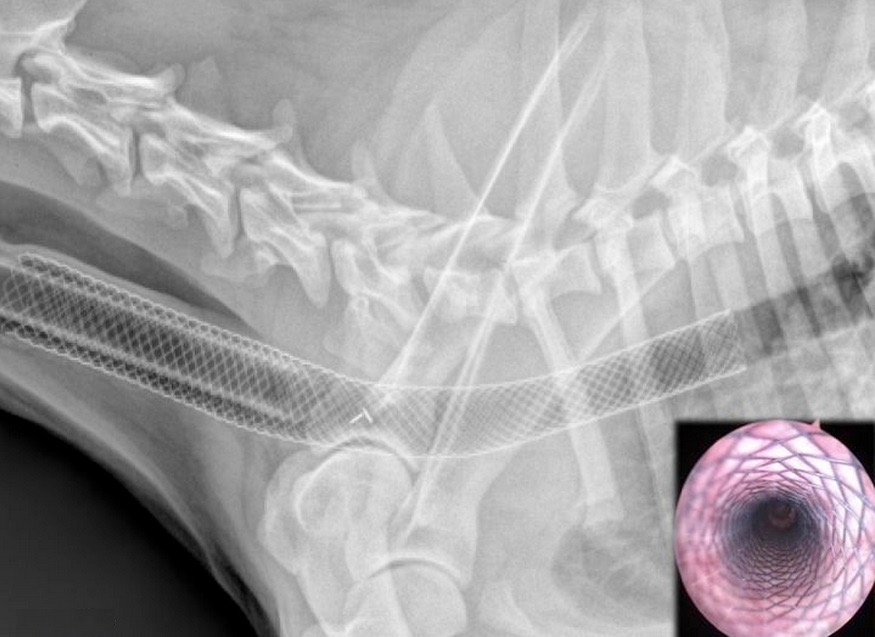

Nous disposons pour cela du Vet Stent‑Trachea®

Il s’agit du seul stent trachéal au monde conçu spécialement pour les applications vétérinaires. S’appuyant sur des milliers de cas cliniques et de nombreuses heures de recherche en laboratoire, ce stent de nouvelle génération est désormais disponible. Il se distingue par sa surface de haute définition qui améliore les caractéristiques de fatigue du stent ainsi que sa biocompatibilité, réduisant ainsi l’inflammation locale.

Le Duality Vet Stent® : le stent de nouvelle génération

Dernier modèle de la gamme Vet Stent-Trachea®, ce stent représente l’aboutissement de nombreuses années de travail en vue de mieux comprendre les mécanismes du collapsus trachéal. Il est destiné aux cas où le diamètre de la trachée varie et il s’adapte ainsi de façon précise au diamètre de la trachée, à la différence des stents standard.

Ce modèle possède une durée de vie et une résistance jusqu’à 400% supérieures aux autres.